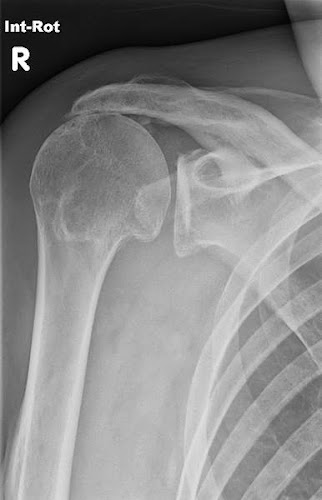

– Ahã. Olha só essa radiografia que a gente tirou no último fim de semana prolongado.

– Nossa, que pulmões. E a faringe, então… Esse pomo de adão, tão proeminente. Que sorte a sua heim, colega. Isso aqui é objeto de estudo pra um simpósio internacional. Merece abordagem multidisciplinar.

– Quando olhei aqueles globos oculares, sem nenhum grauzinho de miopia ou astigmatismo, quase tive uma síncope. Foi adrenalina na veia. Observe essa ressonância magnética. Fala a verdade: que omoplata! Dá pra ficar assintomática? Você sabe que quadros dessa natureza provocam desde espasmos involuntários até a perda momentânea da consciência.